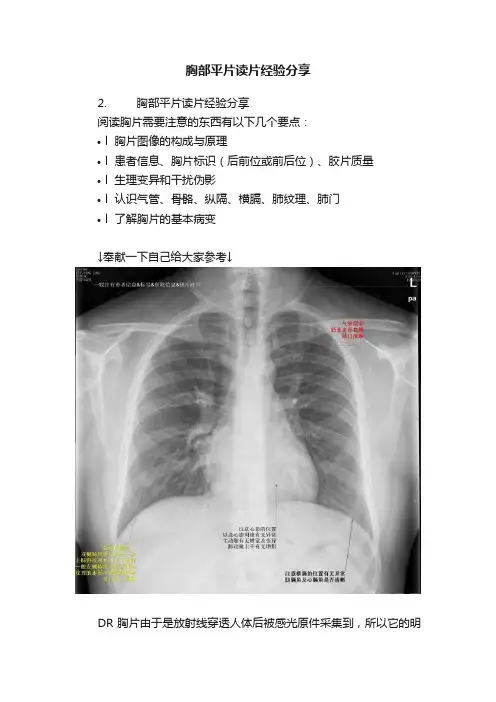

胸部平片读片经验分享2. 胸部平片读片经验分享阅读胸片需要注意的东西有以下几个要点:•l 胸片图像的构成与原理•l 患者信息、胸片标识(后前位或前后位)、胶片质量•l 生理变异和干扰伪影•l 认识气管、骨骼、纵隔、横膈、肺纹理、肺门•l 了解胸片的基本病变↓奉献一下自己给大家参考↓DR胸片由于是放射线穿透人体后被感光原件采集到,所以它的明暗对比取决于被照射组织的密度和其它因素(如马赫效应)构成。

阅读胸片,首先需要核对患者信息,确保这张胶片上的标号和图像是一致的,然后查看图像质量是否合格(体位是否偏斜、吸气是否足够、射线量是否正常、是否有配饰干扰影)一般以双侧锁骨长度、胸锁关节位置以及横膈来快速判断是否有体位偏斜。

正常吸气相胸片,我们会在第5-7前肋看到横膈,可以快速判断吸气是否足够。

正常曝光量的胸片会在心影后方似可见椎体间隙内的软组织,它会模糊不可辨认,当过曝或低曝都会使它无法与周围区别。